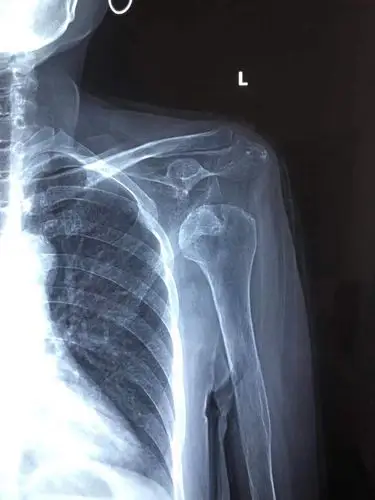

2017年 最后一台手术 陈旧性肩关节脱位 89岁 - 好大夫在线

图 左肩关节x线示左肩锁关节脱位您的满意度:满意基本满意不满意